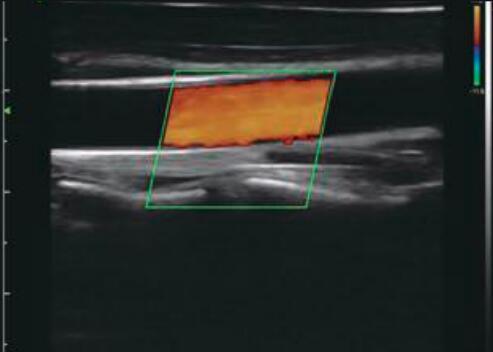

Pocket Ultrasound Scanner Portable Color Doppler Application for MSK Breast Thyroid

This ultrasonic probe was launched in 2018, the probe body has 3 activation buttons, scanning frequency is 7.5-10mhz,

192 elements. Color Doppler wireless linear probe, can provide rapid high-definition ultrasound images for anesthesiologists,

physiotherapists, etc.

Images

Color Doppler Portable Pocket Ultrasound Scanner Application For MSK Breast Thyroid Images |